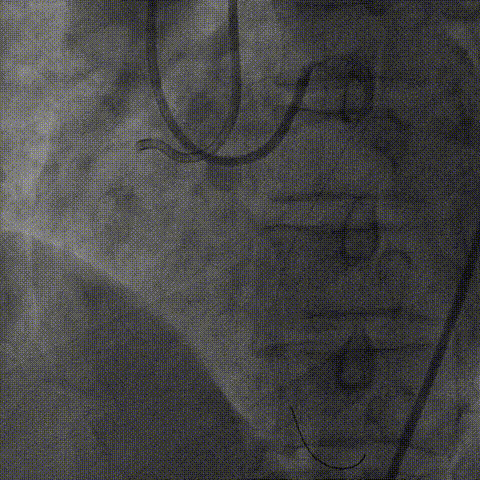

支架植入:

根据血管内超声结果,在Telescope™支撑下序贯植入3.0mm、3.5mm、4.0mm支架3枚,4.0mm直径支架通过Telescope™延长管顺畅,无连接部剐蹭情况。

6F Telescope 支撑下序贯植入Ø3.0 3.5 4.0mm支架,通过性优异

经验体会及总结

闭塞段合并钙化往往给介入术中制造极大困难,导引延长导管的使用可有效提高指引导管支撑力、减少近段血肿形成、并可快速采用AGT技术完成Reverse-Cart 。

6F Telescope™导引延长导管独特的连接部设计可有效提供器械通过性;延长管内腔直径优异,可同时兼容2号2.0mm球囊及Finecross微导管完成球囊锚定下微导管交换,同时延长管可轻松通过4.0mm直径支架,输送效果顺畅。

本例病例中正向失败后转换为逆向,在逆向导丝受阻后又及时转为正向导丝对吻技术完成介入治疗手术,在Telescope™导管支撑下克服病变钙化困难完成支架植入。